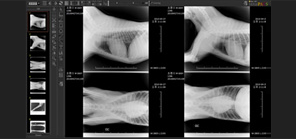

• 의료영상저장전송 시스템

• 다중영상분할 시스템

• 기존 프로그램과 차별화된 직관적이고 간편한 사용자 인터페이스 구현